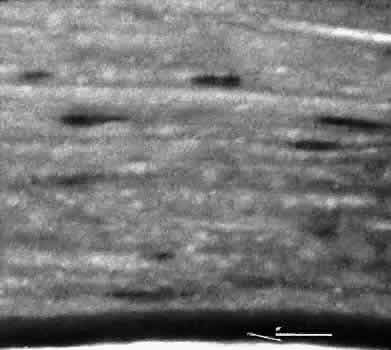

With several microkeratomes, scanning electron microscopy may show a fine undulating contour up to 0.2 mm at the border of the lamellar bed and flap. This feature is formed as chatter lines parallel to the cutting edge of the microkeratome blade (Fig. 19). The frequency of the chatter may relate to the nonlinear pass of the microkeratome. Chatter is absent in rotary keratomes and keratomes using a high oscillation frequency.66–68

Fig. 19. Scanning electron microscopy of the lamellar bed in LASIK. A. At the edge of the wound, oscillation marks caused by some types of microkeratome can be identified. B. The lamellar bed in the center of the wound is moderately irregular.